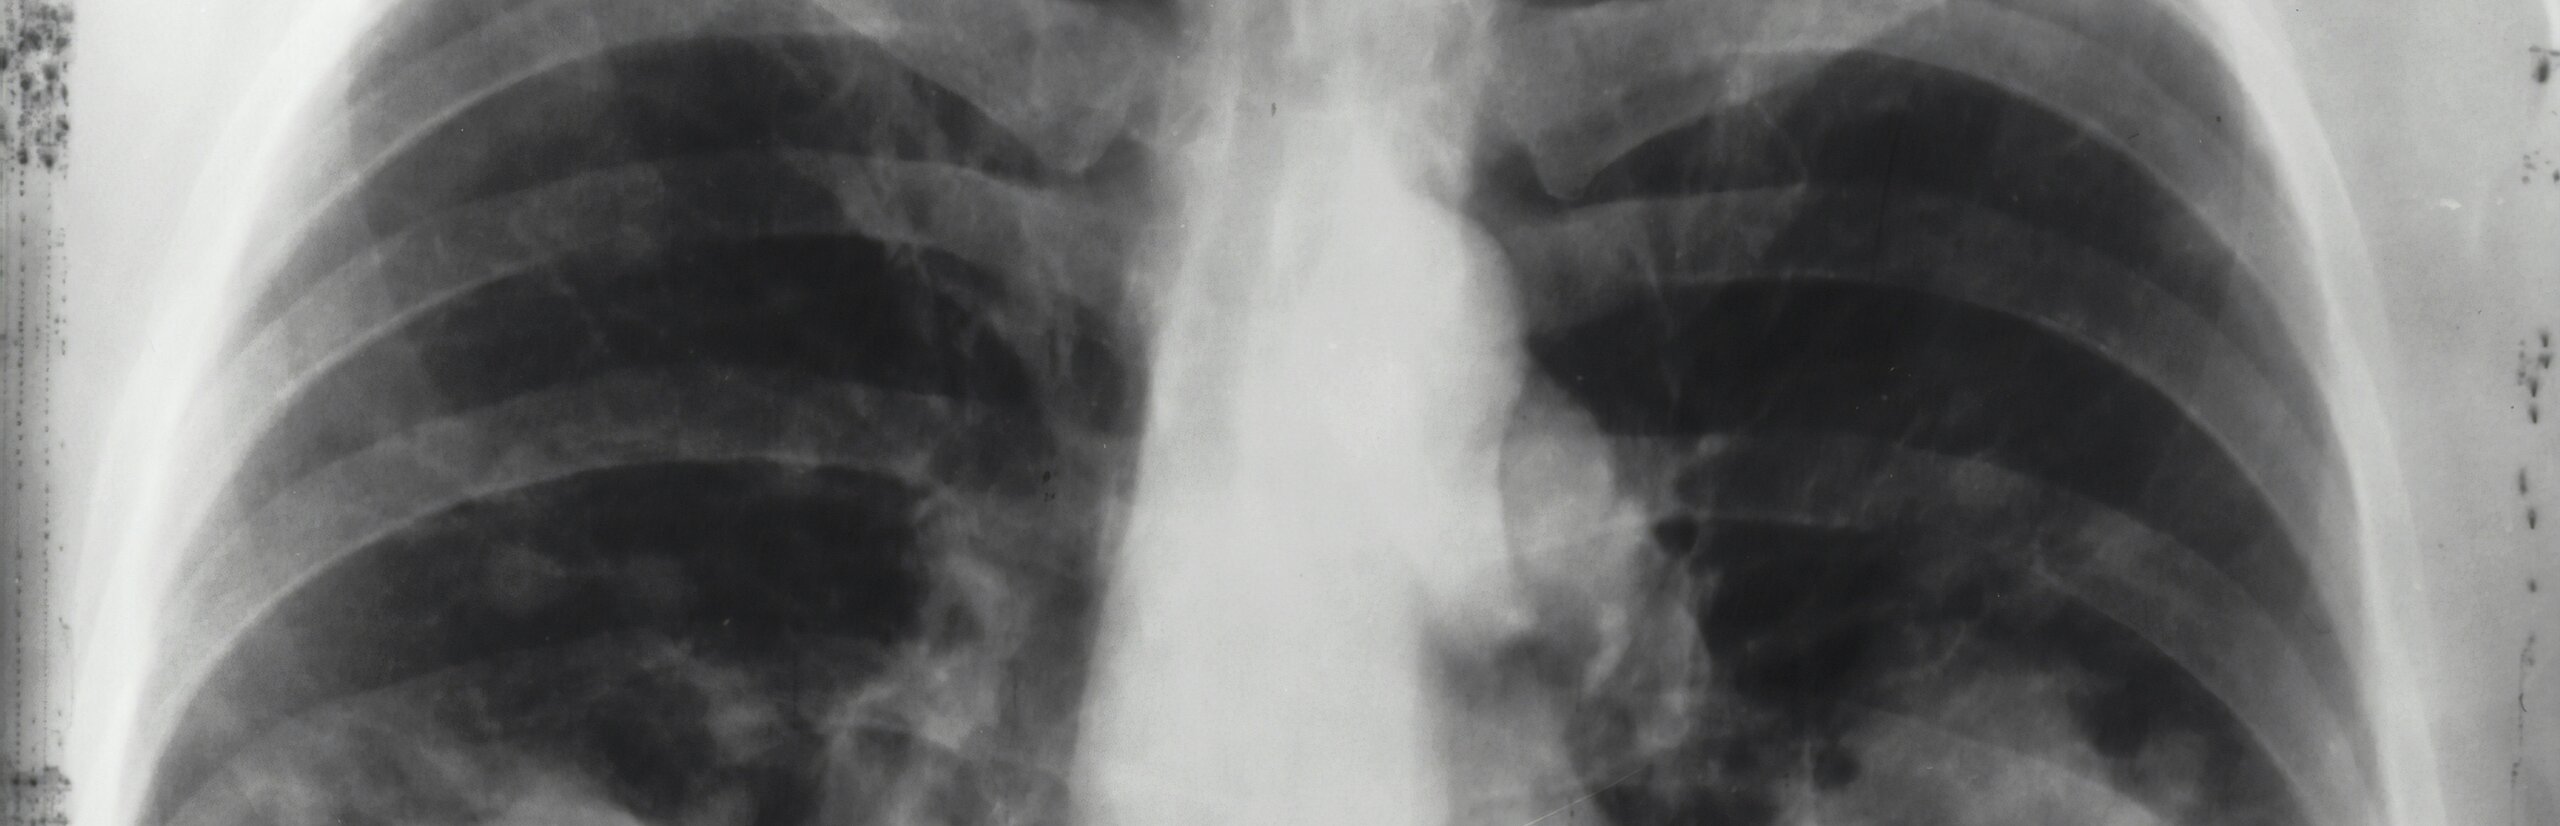

- Lungenkrebs (Thorakale Onkologie)

- Lungenhochdruck (Pulmonale Hypertonie)

- Vernarbungen der Lunge (Interstitielle Lungenerkrankungen)

- Chronisch obstruktive Lungenerkrankung (COPD)

- Asthma bronchiale

- Seltene Lungenerkrankungen